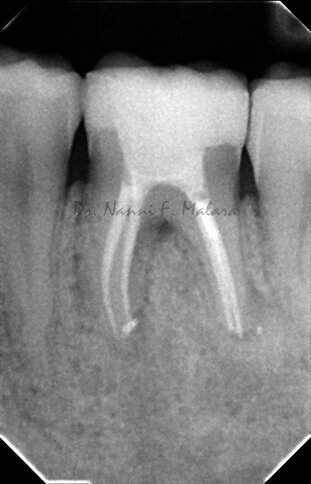

Controllo della guarigione a 7 mesi dalla terapia endodontica (Alla radiografia si nota come le lesioni ossee siano guarite, e la densità della trabecolatura ossea sia tornata alla normalità)